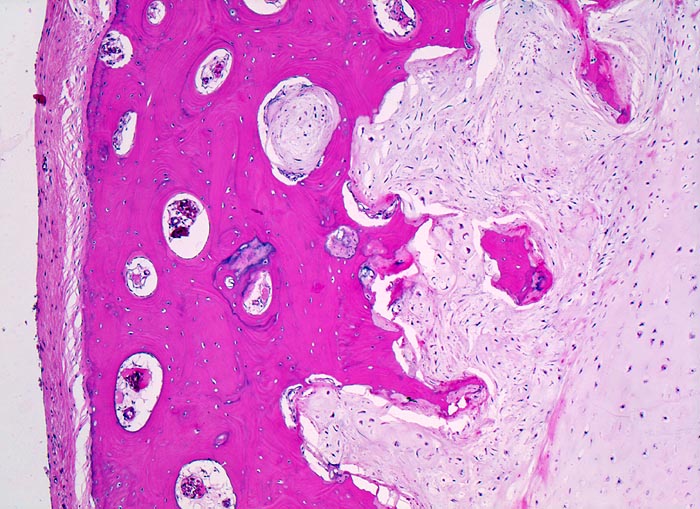

Chondrosarkom: Invasion der Kortikalis

Knochen, Rippe

Kortikaler Knochen bedeckt von Periost. Das Sarkom (rechts im Bild) infiltriert und destruiert die Kortikalis. Im Bereich der Invasionsfront ist die Zellularität leicht gesteigert.

Umschriebene Schmerzen im Bereich des Rippen-Thorax seit über einem Jahr.